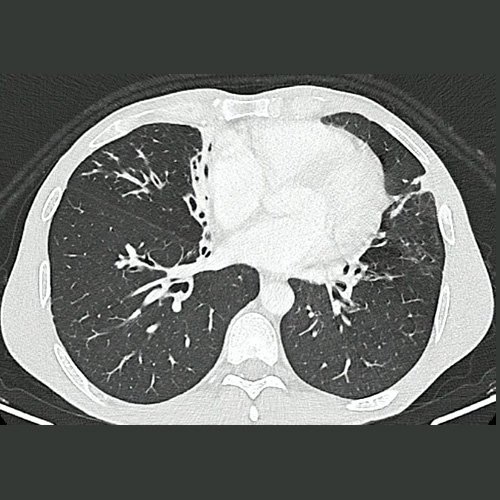

• TAC de tórax con contraste EV (DÍA 1): Persiste adenopatía mediastinal subcarinal de 16 mm de diámetro en su eje corto. El resto de los ganglios mediastinales visibles son de tamaño y morfología normal. El árbol traqueobronquial no presenta alteraciones. El análisis del parénquima pulmonar muestra múltiples pequeñas bronquiectasias de paredes gruesas, asociadas a discreto patrón de árbol en brote y a pequeñas atelectasias laminares subsegmentarias, en segmento anterior del lóbulo superior derecho, lóbulo medio, segmentos lingulares, y segmentos basales de ambos lóbulos inferiores. Hallazgos ya presentes en estudio anterior.

Tomografía de tórax (Ventana pulmonar-corte axial) DÍA 1